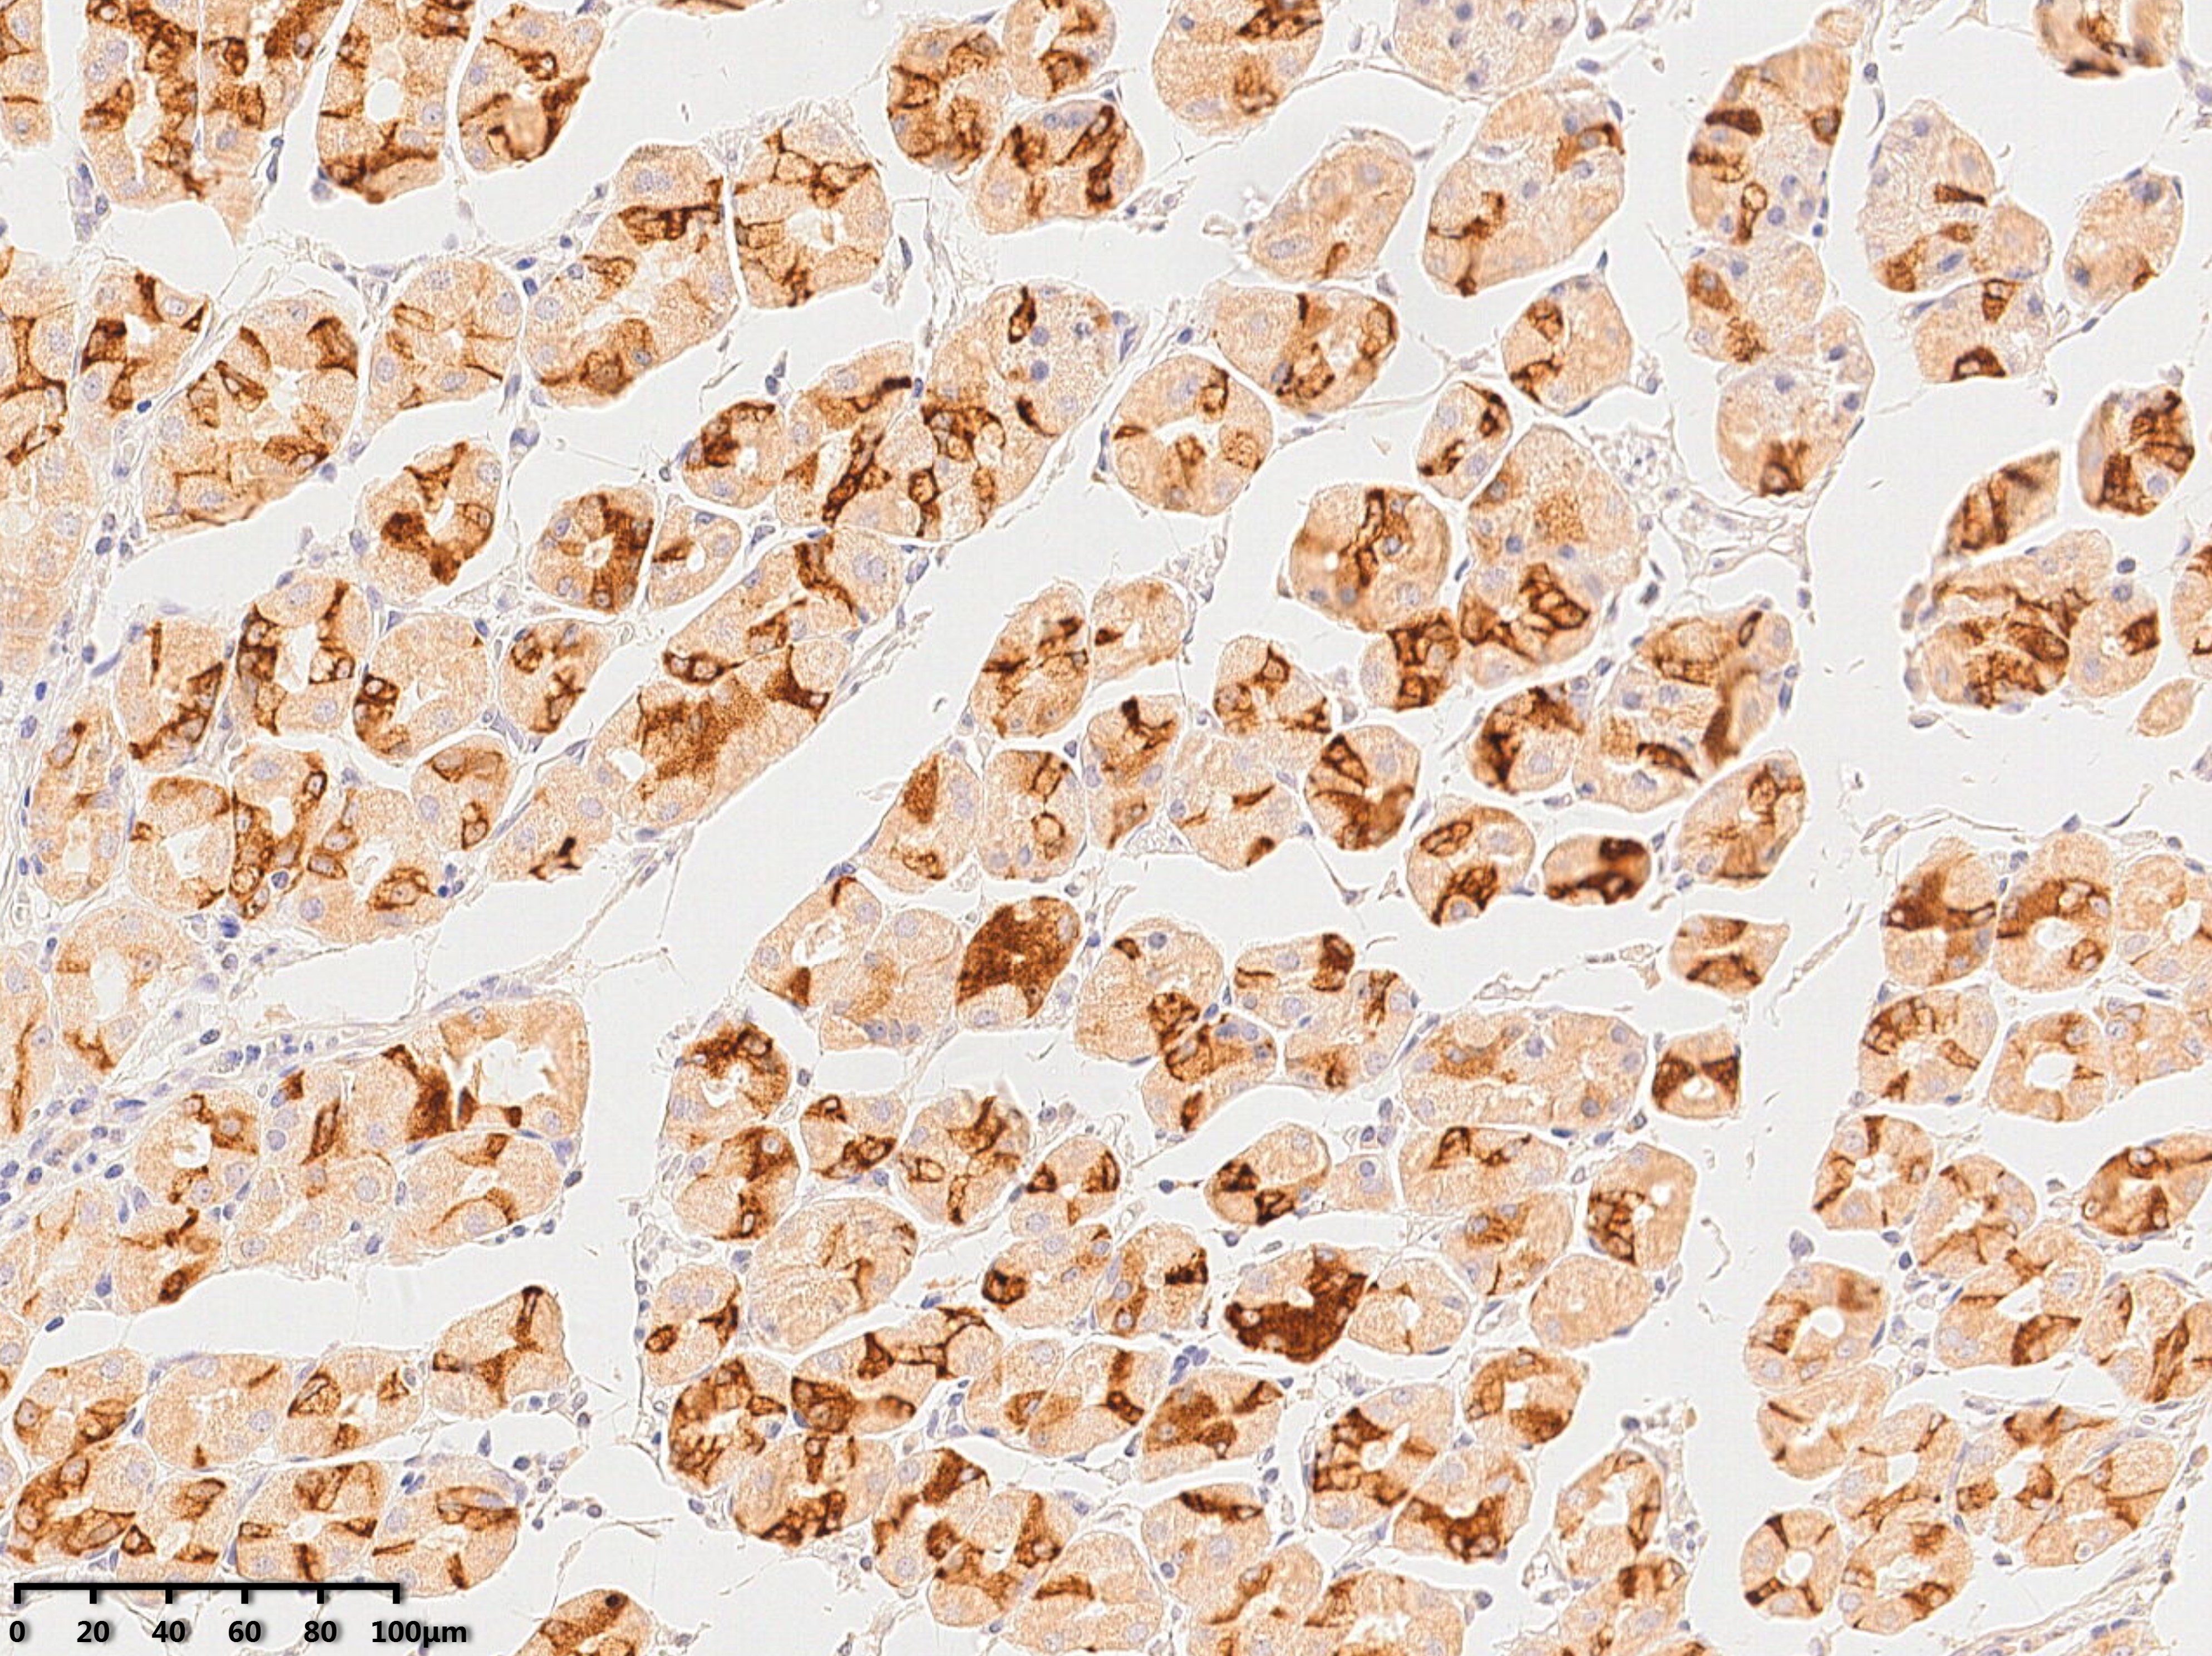

不同于市场上常见的多克隆抗体或针对短肽段的抗体,傲锐东源的单克隆抗体以全长人重组蛋白为抗原,因此能识别蛋白质在天然状态下的构象表位。这使得其抗体在免疫组化(IHC)、免疫荧光(IF)、流式细胞术(FC)等应用中,具有更高的灵敏度和更低的背景噪音。

鼠单克隆(TrueMAB)和兔单克隆(TrueRAB)两大系列。经过严格的特异性验证,涵盖免疫组化、Western Blot、流式细胞术等多种应用。针对热点靶点如MDA5、PLA2R1、PCNA等推出了人源化质控品抗体。

免疫组化(IHC):需进行抗原修复(热修复或酶修复),以暴露被福尔马林掩盖的抗原表位。

解决:使用全长蛋白作为抗原制备的抗体,能识别构象表位,且经过KO/KD验证(部分产品),显著降低交叉反应。